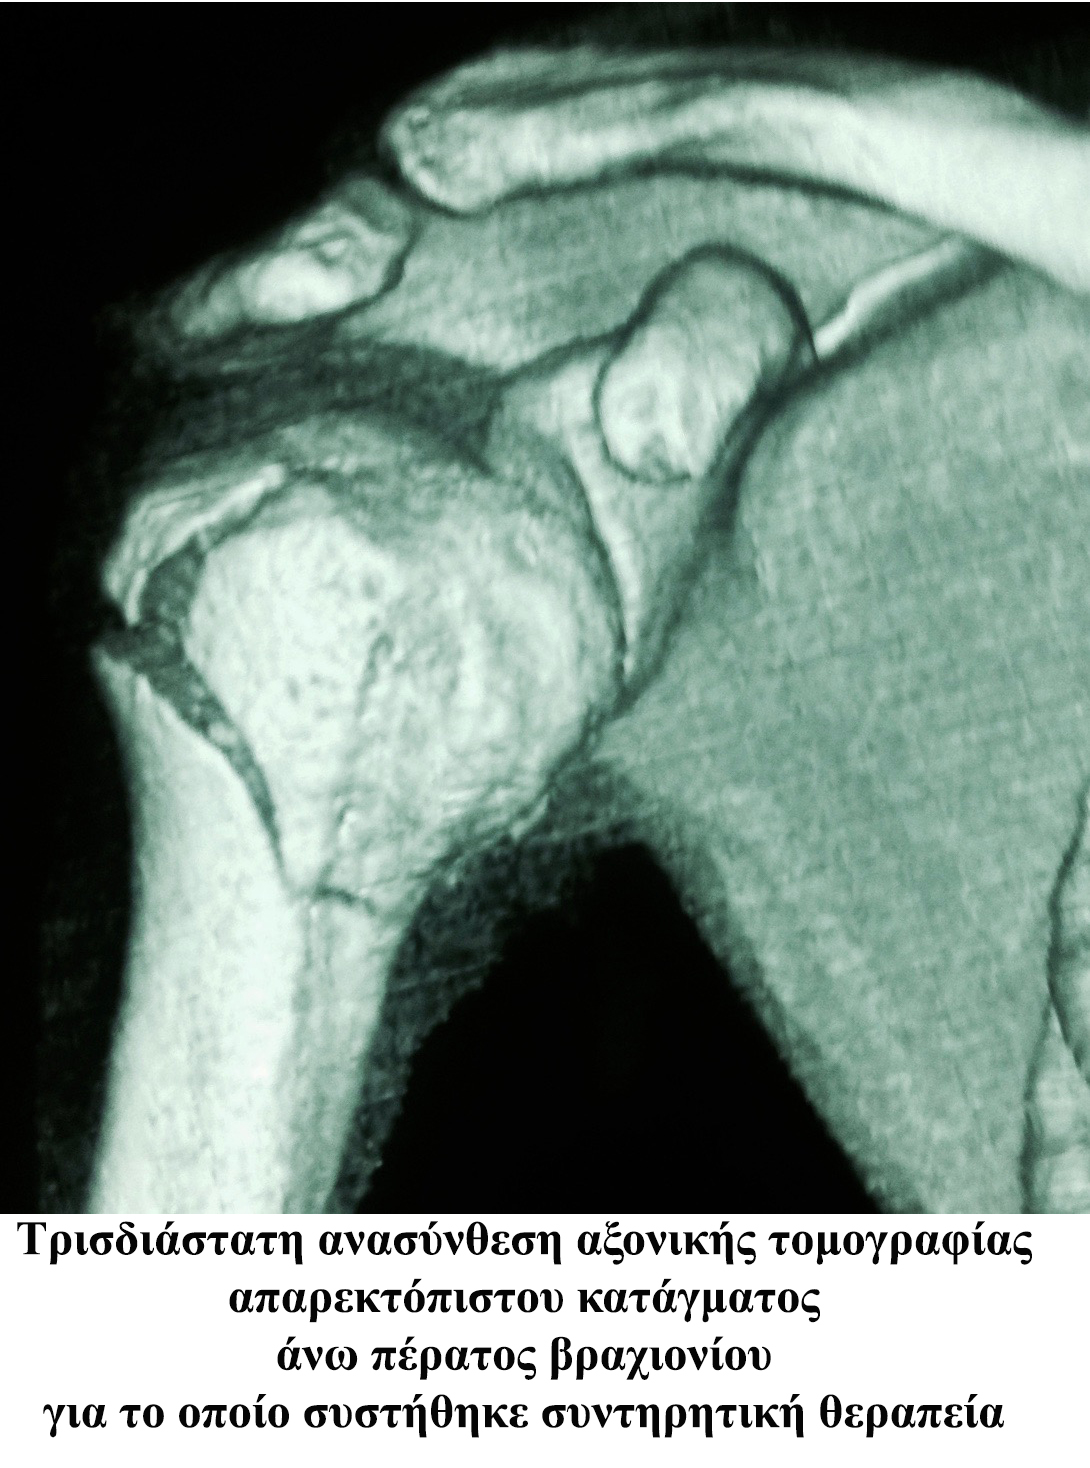

Σε περίπτωση μη παρεκτοπισμέων καταγμάτων η συντηρητική θεραπεία προτείνεται συχνά. Ωστόσο συνεχής ακτινολογικός έλεγχος και προσεκτική κινησιοθεραπεία του ασθενή είναι απαραίτητη.